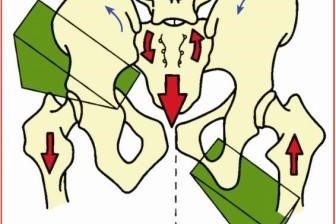

Nuestro curso miofascial es nuestra más reciente promesa formativa que busca impartir una metodología para evaluar, edificar y reprogramar la postura en función de la Biomecánica Global de las Cadenas Miofasciales. Todo esto a través del conocimiento del origen del dolor y su correspondiente estudio. ¿A quiénes va dirigida nuestra formación miofascial? Dado que…